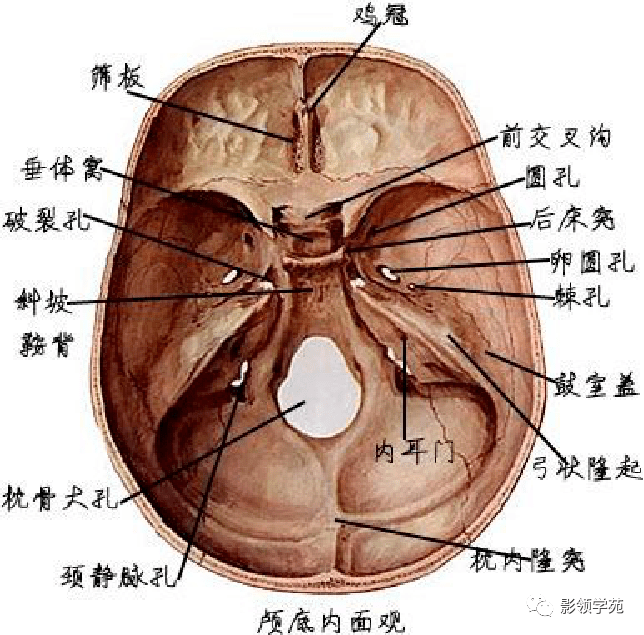

骨骼系统

骨骼系统